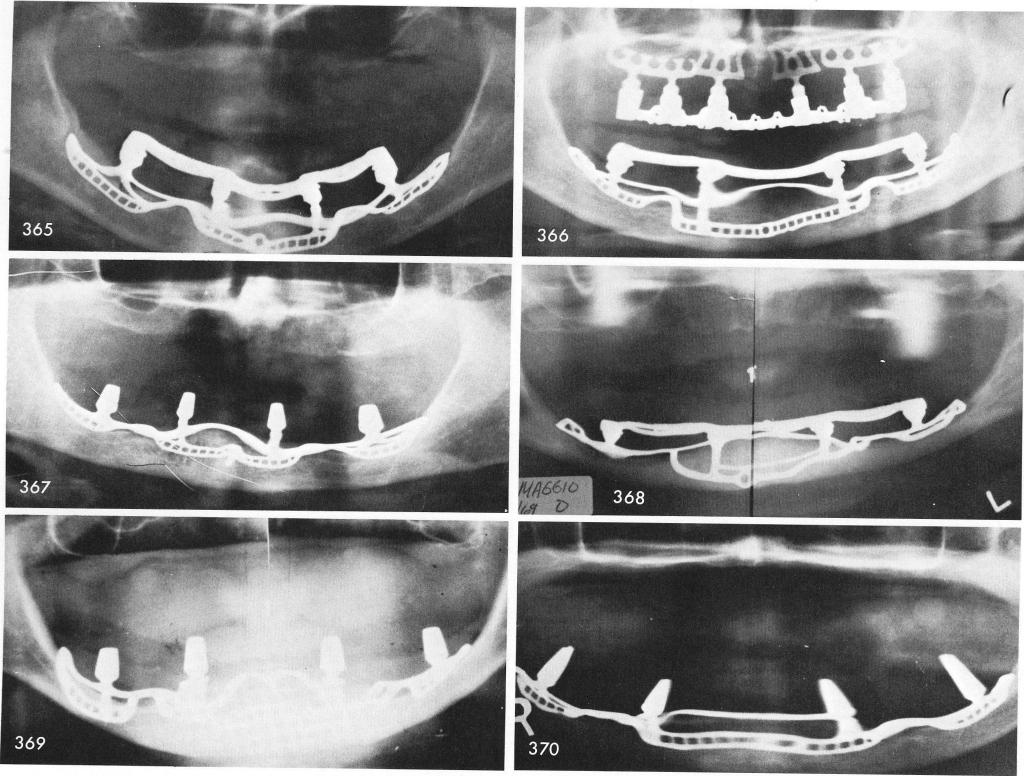

Mandibular Implants (published 1977)   Dr. Leonard I. Linkow